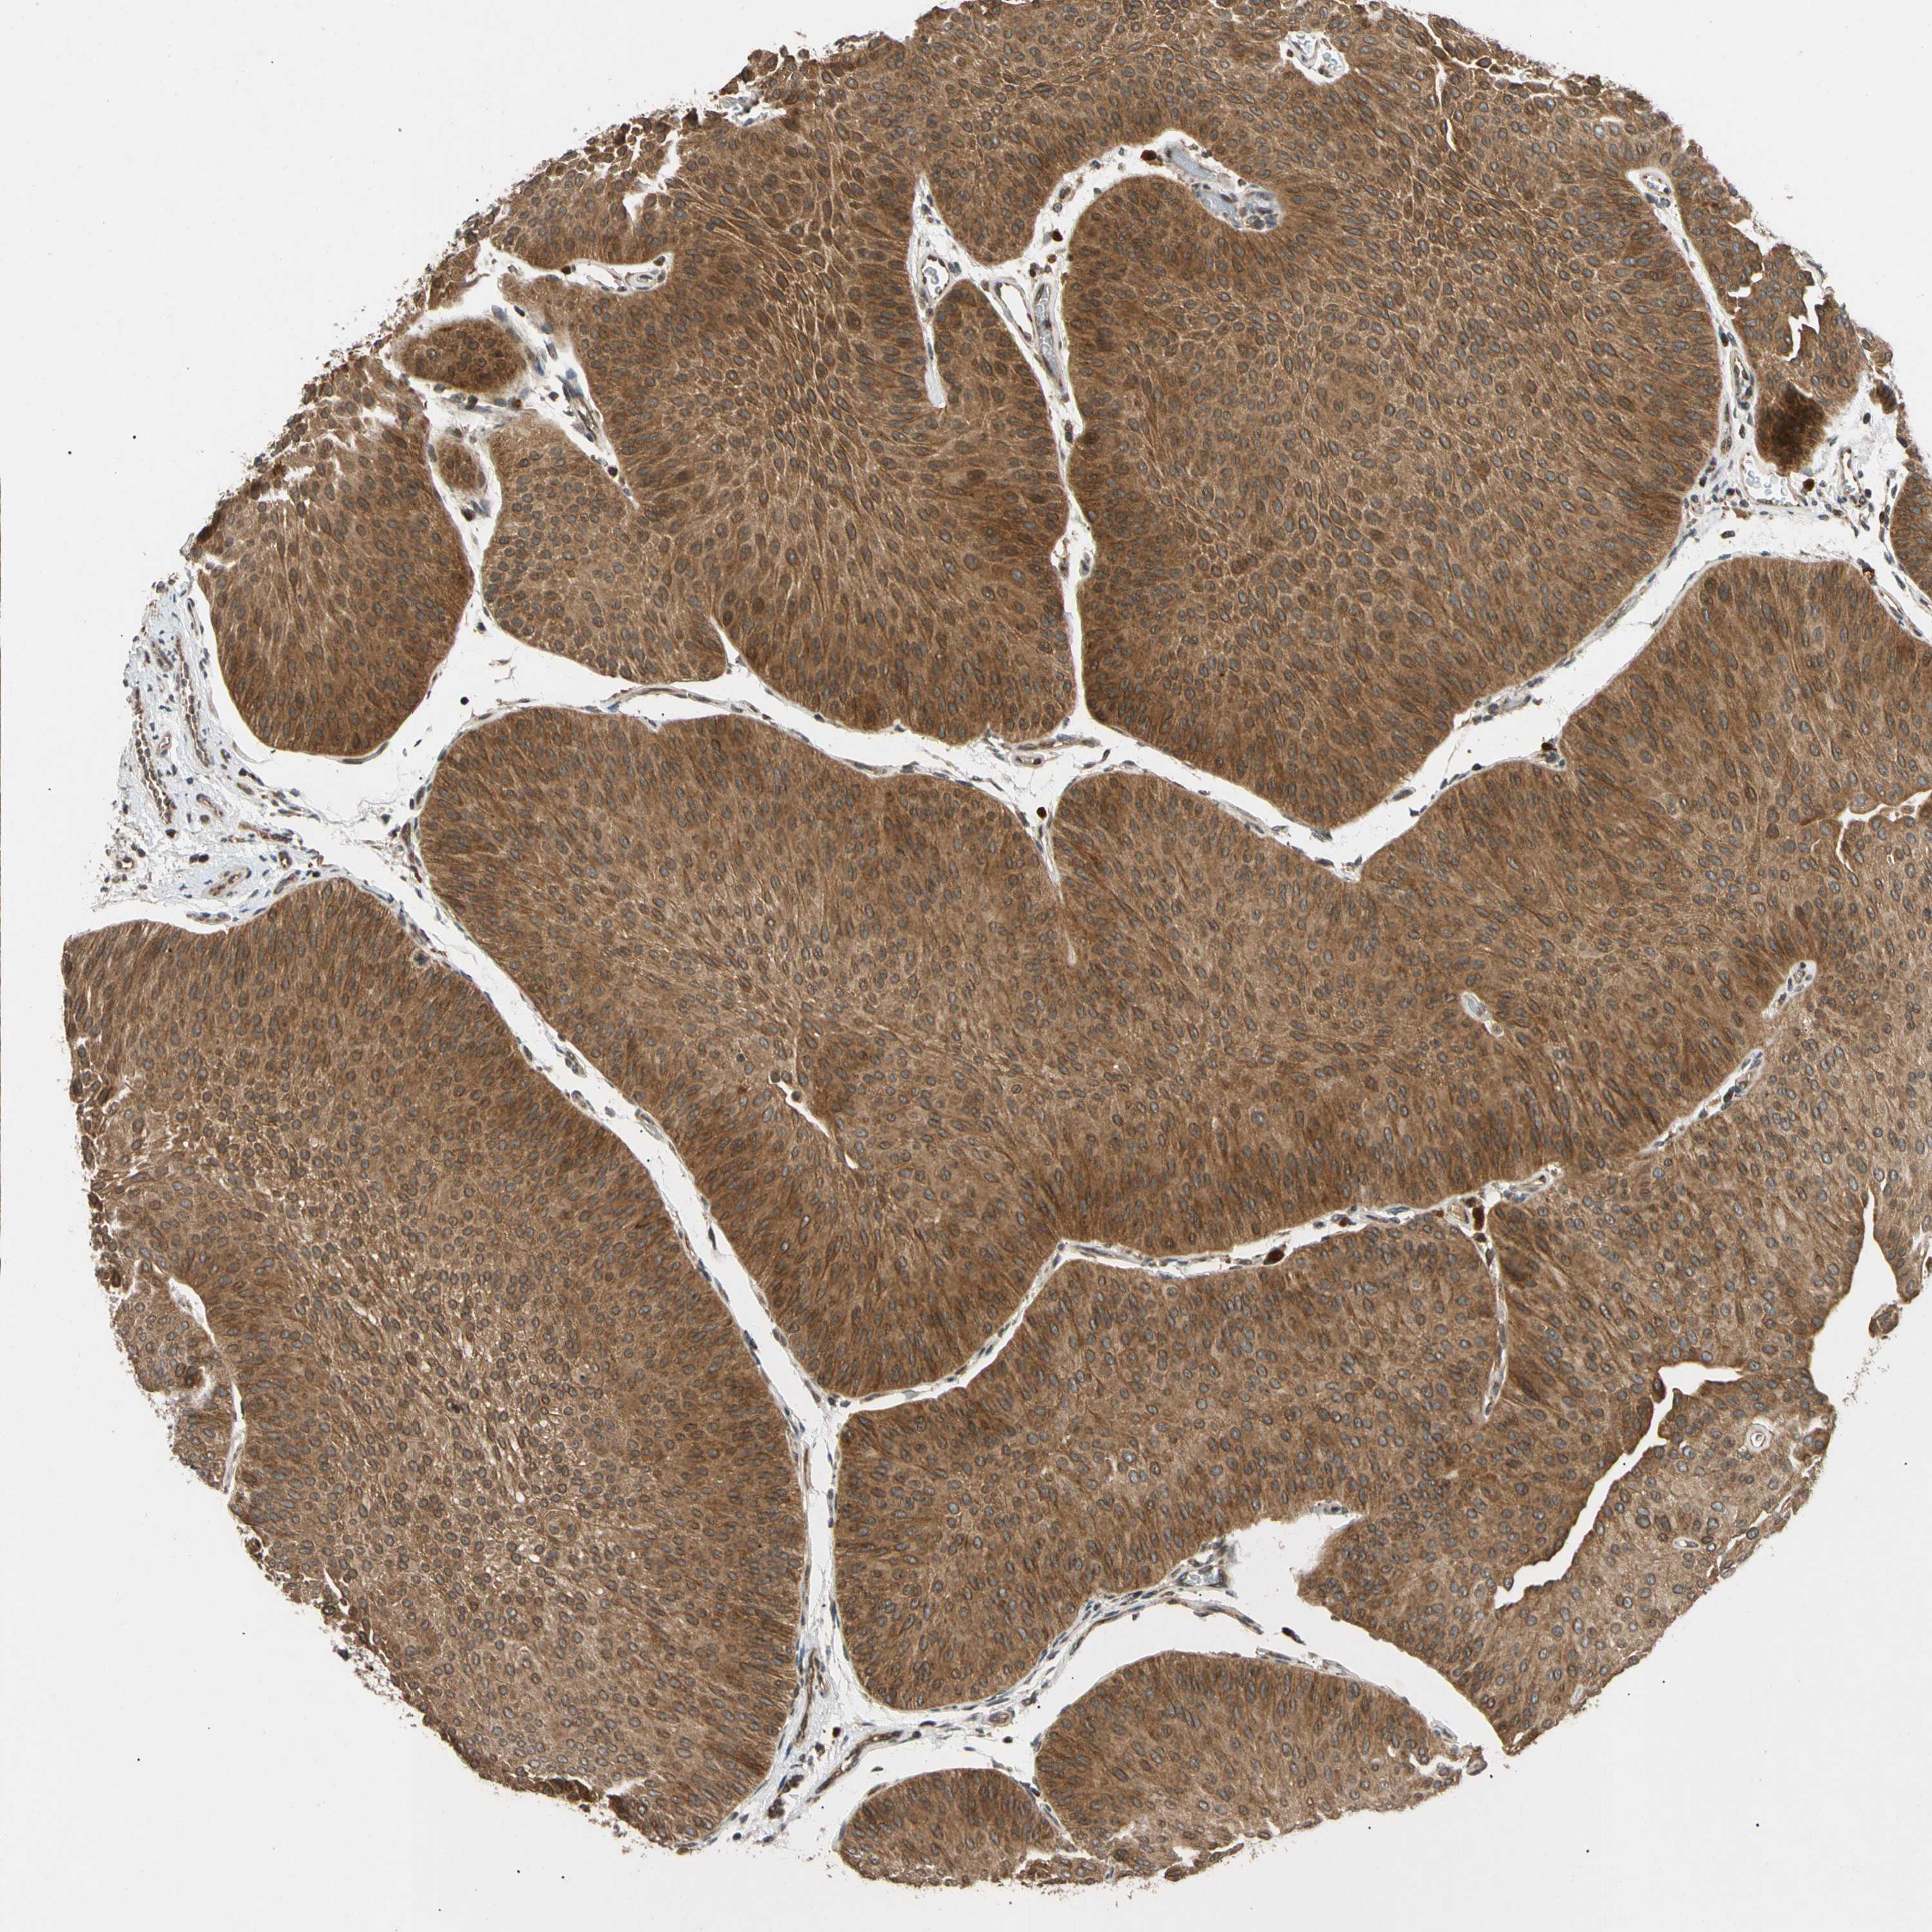

UROTHELIAL CANCER - Protein expressioni

A mouse-over function shows sample information and annotation data. Click on an image to view it in a full screen mode. Samples can be filtered based on level of antibody staining by selecting one or several of the following categories: high, medium, low and not detected. The assay and annotation is described here.

Note that samples used for immunohistochemistry by the Human Protein Atlas do not correspond to samples in the TCGA dataset.

Antibody stainingi

Antibody staining in the annotated cell types in the current human tissue is reported as not detected, low, medium, or high, based on conventional immunohistochemistry profiling in selected tissues. This score is based on the combination of the staining intensity and fraction of stained cells.

Each image is clickable and will lead to virtual microscopy that enables deeper exploration of all samples and also displays staining intensity scores, fraction scores and subcellular localization as well as patient and tissue information for each sample.

Antibody HPA006083

Antibody HPA007830

Urothelial carcinoma, High grade

Urothelial carcinoma, Low grade